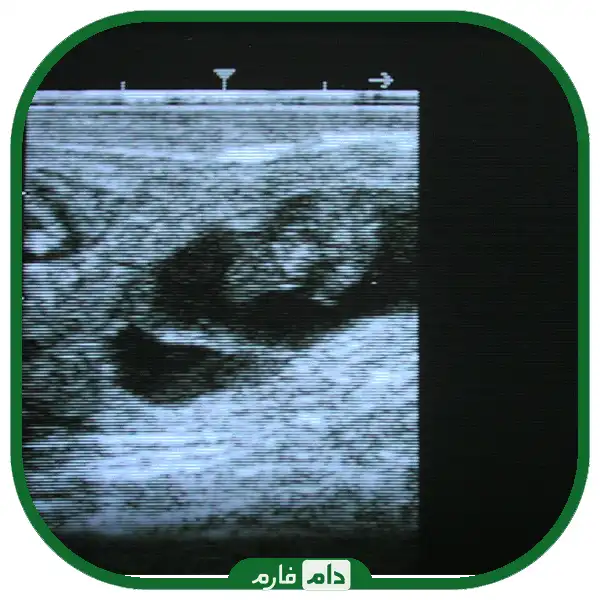

دو روش معاینه ترانس رکتال، لمس رکتوم و سونوگرافی، هر دو ساختارهای مشابهی را تشخیص می دهند - جنین، مایع و غشای جنین. هر کدام مزایای خاص خود را دارند. لمس رکتوم نیازی به تجهیزات گران قیمت یا منبع تغذیه ندارد. از نظر زمان برای تعداد کمی گاو و برای بارداری های دیررس مزایای قابل توجهی دارد. سونوگرافی به تجهیزات گران قیمت نیاز دارد، اما برای تعداد زیادی از گاوها سریعتر است و گوساله ها می توانند با دقت بیشتری پیر شوند، به ویژه در مراحل اولیه و همچنین می توانند از 55 روزگی به بعد جنسیت شوند. برای یک دامپزشک باتجربه، تفاوت کمی در دقت بین تشخیص حاملگی با لمس و سونوگرافی وجود خواهد داشت، زیرا بیش از 95٪ گاوهای خالی و باردار به درستی شناسایی می شوند.

معاینه ترانس رکتال را می توان از حدود 20 روز پس از تلقیح انجام داد، اما دقت در این مرحله بسیار کمتر است، و زمان صرف شده برای هر گاو بسیار بیشتر از معاینات پس از 30+ روز است، بنابراین زمان استاندارد برای معاینه حدود 35 روز است.

سونوگرافی برای افزایش سن و جنسیت جنین بهتر است.